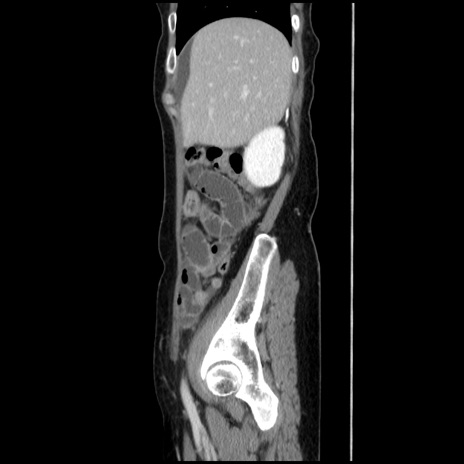

冠状断像